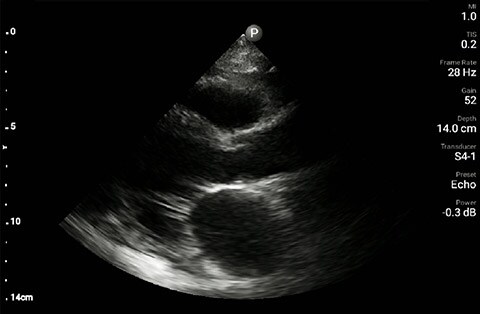

In this Lumify case study and summary video, Dr. Sara Nikravan discusses how she used her Philips Lumify handheld ultrasound system to guide the diagnosis and treatment of a patient experiencing shortness of breath.

Determining the cause of respiratory distress in the acutely ill can be challenging. POCUS with a three-point exam (F-TTE, IVC collapsibility, and lung ultrasound), as performed above, has been endorsed in this patient population as it can increase diagnostic accuracy in a timely fashion, especially as it pertains to acute decompensated heart failure.4 Furthermore, the use of a small portable device allows for convenience with rapid setup and use while minimizing the uptake of space. This becomes especially important when caring for patients that often have many providers attempting to provide care and initiate interventions at the same time, given the acute nature of their illness and potential for further rapid de-compensation.